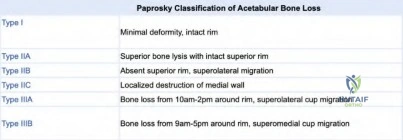

A 72-year-old male with a history of a cemented total hip arthroplasty (THA) 15 years ago presents with persistent groin pain and aseptic loosening of the acetabular component. Radiographs show significant acetabular osteolysis and a Paprosky Type IIIB defect.

Which of the following is the MOST appropriate reconstructive option for this acetabular defect?